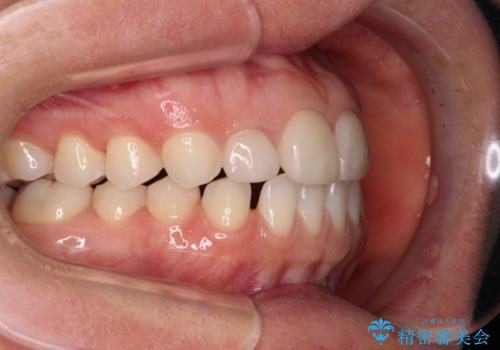

前歯を綺麗にしたい 部分矯正とセラミック治療

- 大きすぎる上顎前歯と、隙間の空いた下顎歯列を気にして来院された患者様です。

上顎前歯にはセラミッククラウンが装着されており、顔や他の歯と比較して幅の大きい状態でした。

下顎前歯は空隙歯列弓であったので、アンカースクリューとワイヤー装置を用いてスペースを閉じていくこととし、上顎前歯は矯正治療用の仮歯に置き換えた上で、仮歯の大きさを削って小さくしながら、上下前歯部の部分矯正を行うこととしました。

矯正治療後は、仮歯とした上顎前歯をオールセラミッククラウンにて補綴治療を行うこととしました。

日本と海外を拠点に仕事をされていらっしゃるため、数ヶ月治療があいてしまうことがあり、期間はかかりましたが、2年間で望み通りの前歯に仕上げることができました。